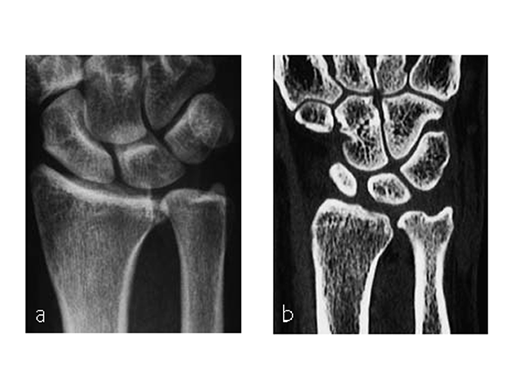

A 69-year-old female patient had suffered a right distal radius fracture one year earlier, and received conservative management. Symptoms included pain and impaired function about the wrist and forearm, with decreased forearm rotation. Painful DRUJ (DASH: 34, PWRE: 29).

The amount of correction required was 2.5 mm. The preoperative x-ray showed positive ulna variance.